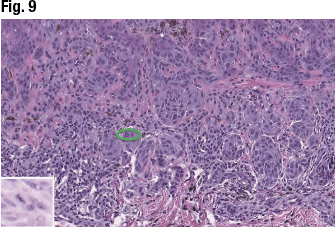

In another case, a 14-year-old female presented with a brown lesion on her right lower abdomen. The asymmetrical but circumscribed proliferation of epithelioid melanocytes is seen in Fig. 6. The cells are arranged with larger nests in the superficial dermis and epidermis (Fig. 7), and Dr. Aung noted the irregularly dispersed pigments and lymphoid aggregates at the base of the lesion. Fig. 8 shows the pagetoid migration of melanocytes at the periphery of the lesion and Kamino bodies, “which are supposed to be seen more frequently in benign [lesions], so this lesion is showing both benign and malignant morphologic features,” she said. In high power (Fig. 9), “this lesion failed to show a maturation pattern.” Some of the lesional cells showed cytologic atypia with pleomorphism, including scattered mitotic figures within the dermis.